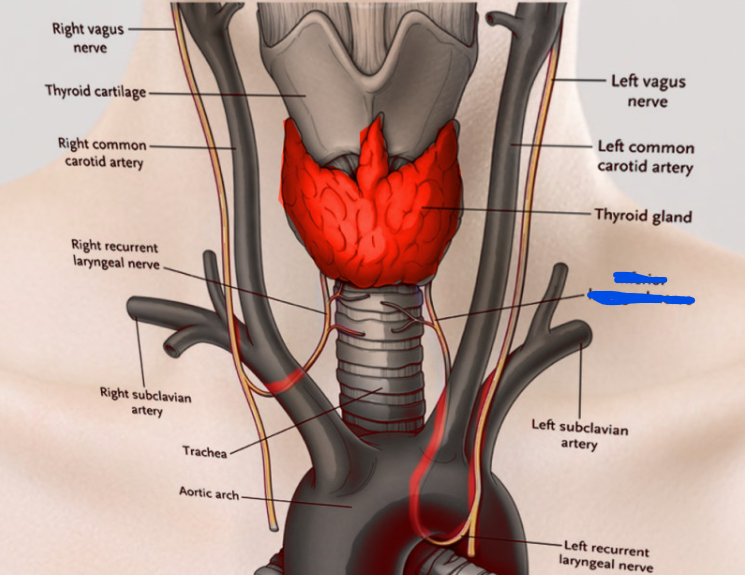

Vagus n. (CN X)

Name the nerve

Superior laryngeal n.

Name #3

Internal branch of superior laryngeal n.

Inferior laryngeal n.

Name the left recurrent laryngeal n.

Left recurrent laryngeal n.

Name the right recurrent laryngeal n.

Right recurrent laryngeal n.

Know the common carotid a.

Common carotid a.

Know the internal carotid a.

Internal carotid a.

Know the external carotid a.

External carotid a.